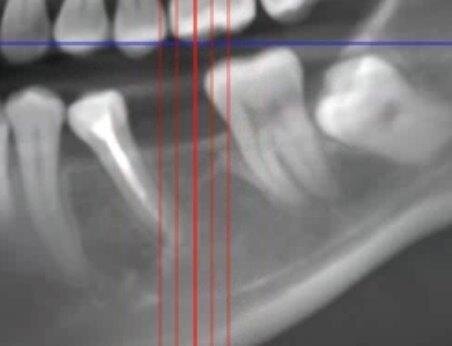

Nello studio sono stati inclusi 20 pazienti (12 donne e 8 uomini) di età compresa tra i 28 e i 65 anni, con edentulia singola e conseguente deficit vestibolare dei tessuti molli. La matrice dermica a elevata consistenza è stata opportunamente ritagliata mediante forbici e lama ed è stata posizionata al di sotto del lembo muco periostale allestito con approccio a spessore totale, vestibolarmente alla cresta ossea in cui è stato posizionato contestualmente un impianto endosseo osteointegrabile. Non si è utilizzato alcun ausilio di fissazione per la matrice dermica che è stata stabilizzata dal solo lembo di accesso ribaltato su di essa e suturato, mediante punti staccati semplici, al lembo linguale.

Le rilevazioni eseguite a distanza di 18 mesi di tempo medio, hanno mostrato un netto miglioramento del PES (Pink Esthetic Score) con un punteggio medio superiore a 9 (eccellente) e in due casi un punteggio tra 6 e 8 (buono). La sovrapposizione dei file .stl provenienti dalla scansione della arcata dentaria interessata prima dell’intervento e a distanza di 18 mesi ha permesso di rilevare un incremento medio in senso orizzontale di 2 mm in media.